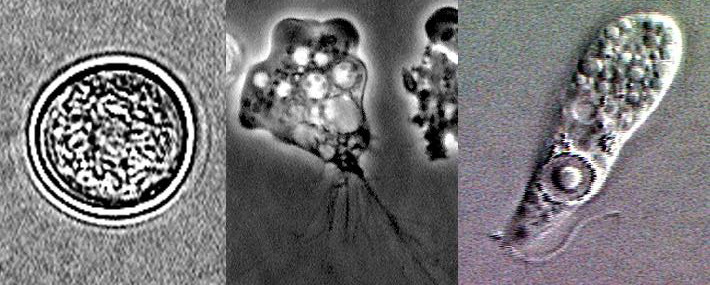

The Centers for Disease Control and Prevention confirmed the child’s illness was caused by Naegleria fowleri, an amoeba found in freshwater. It can be fatal if forced up the nose, as can occur during jumping into water, diving, water-skiing or other water activities.